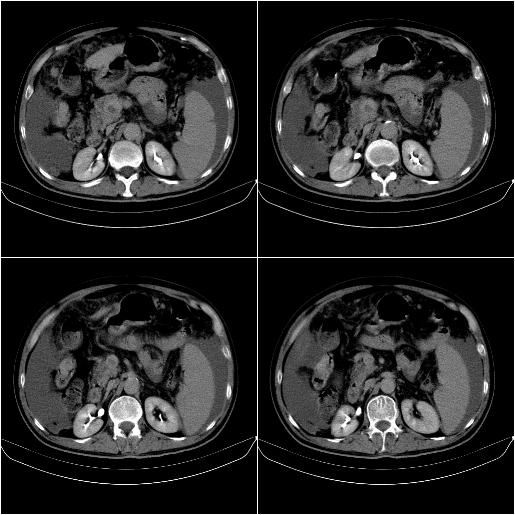

标题: CT21651:M,67Y,肝癌9月,介入术后3月。

m,67y,肝癌9月,介入术后3月。现腹胀、纳差、腹泻。

脾脏转移。。。

1)肝癌介入治疗术后碘油沉积不良。2)门静脉瘤栓形成,腹膜广泛性转移。3)肝硬化,脾大,腹水。4)慢性胆囊炎。